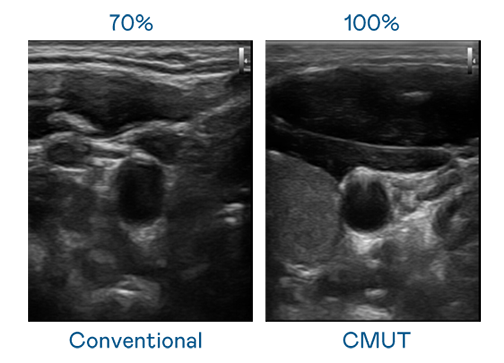

CMUT 技术是一种用电容式微机电元件来产生超音波讯号的技术。与传统 PZT 压电式技术相比,CMUT 频宽增加 30%,更宽频的超音波讯号让影像解析度大幅提升,是实现高影像品质医疗超音波扫描、促进精准医疗发展的关键技术。

大频宽带来超清晰影像

超音波影像的解析度高低,首先取决于探头能发出的讯号频宽。XPJ·(中国区)官方 CMUT 可提供高清晰的超音波讯号,提供高频宽、高灵敏度、影像纹理细节更高的超音波影像,协助医护人员缩短影像判读时间及利用精准的医疗影像进行诊断。